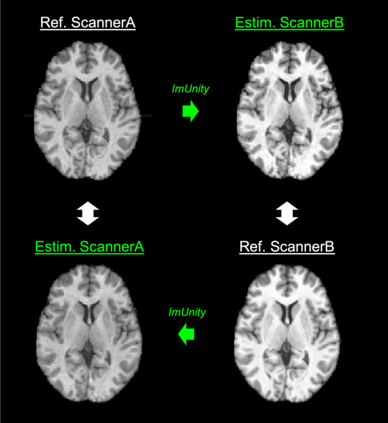

ImUnity is an original deep-learning model designed for efficient and flexible MR image harmonization. A VAE-GAN network, coupled with a confusion module and an optional biological preservation module, uses multiple 2D-slices taken from different anatomical locations in each subject of the training database, as well as image contrast transformations for its self-supervised training. It eventually generates 'corrected' MR images that can be used for various multi-center population studies. Using 3 open source databases (ABIDE, OASIS and SRPBS), which contain MR images from multiple acquisition scanner types or vendors and a large range of subjects ages, we show that ImUnity: (1) outperforms state-of-the-art methods in terms of quality of images generated using traveling subjects; (2) removes sites or scanner biases while improving patients classification; (3) harmonizes data coming from new sites or scanners without the need for an additional fine-tuning and (4) allows the selection of multiple MR reconstructed images according to the desired applications. Tested here on T1-weighted images, ImUnity could be used to harmonize other types of medical images.